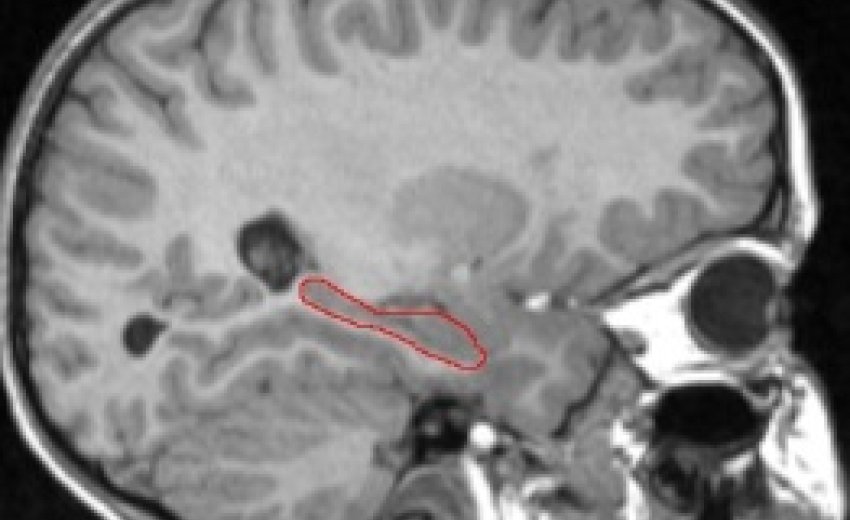

Hippocampus Outlined in Red (T1-weighted MRI image)

We are currently examining whether the effect of hypoglycemic episodes is visible in brain regions associated with memory, especially the hippocampus (see picture below). The hippocampus is a cashew-shaped gray matter structure known to play a role in the "consolidation" of memory, or the conversion of short term into long term.